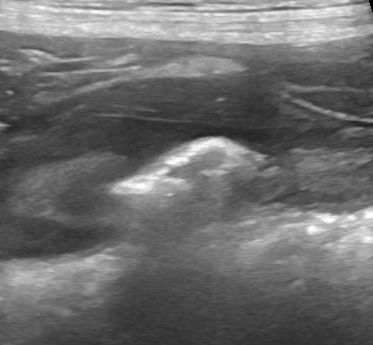

This is the second dog I’ve seen with presumed immune-mediated thrombocytopaenia treated with high doses of prednisolone which developed marked hepatomegaly accompanied by significant volume of ascites. Both cases received a total daily oral prednisolone dose of 4mg/Kg and developed ascites consisting of modified transudate within one week. Sonographically the liver was markedly enlarged and … Continue reading